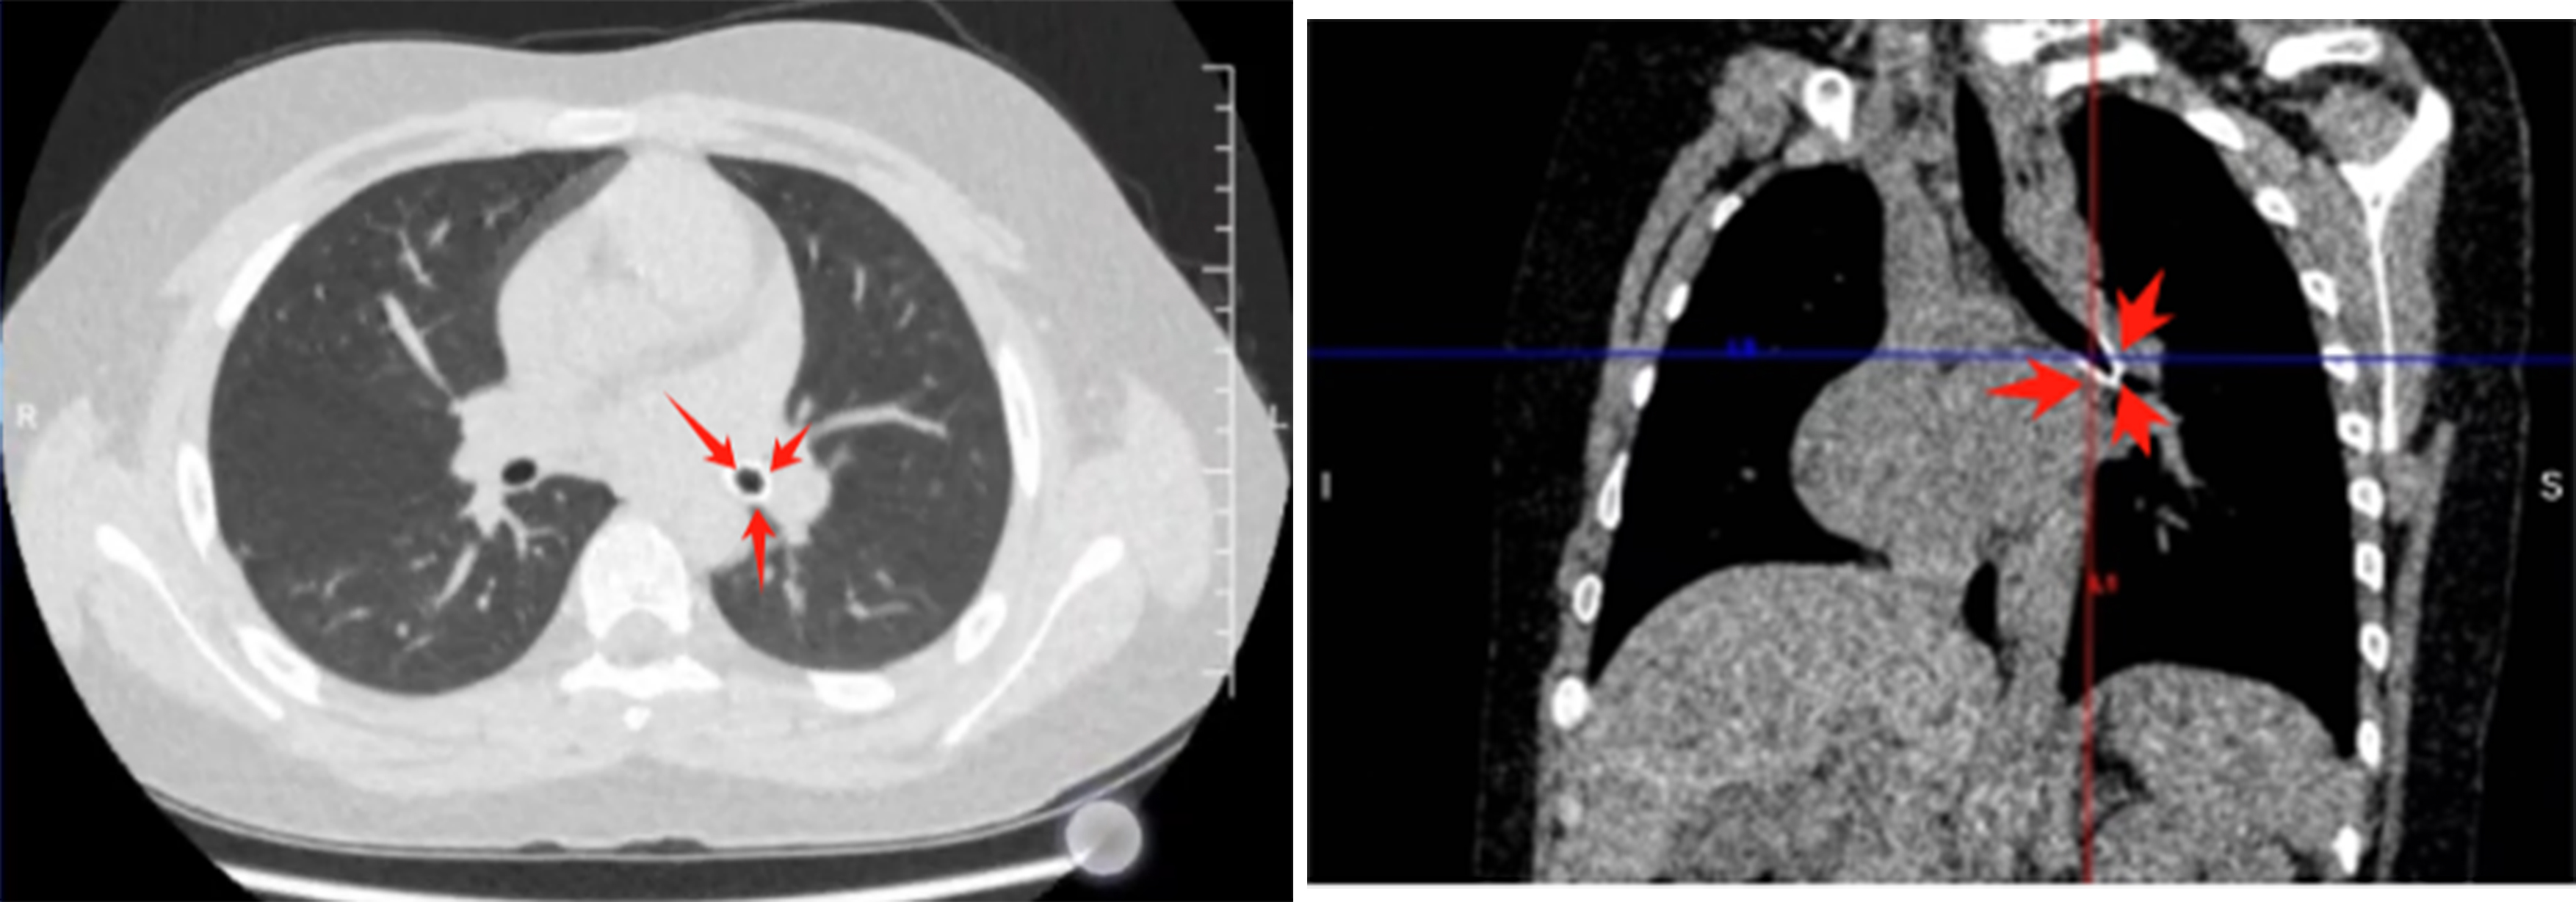

10月14日,家住威海的九岁小朋友涵涵(化名)课间无聊,将中性笔的笔头旋转下来,含在口中玩耍,结果不慎将其误吸入气道,当地医院做的双肺CT检查显示孩子的左肺主支气管远端见异物阻塞气道,于是紧急联系烟台山医院东院儿科主任李海燕。

结合涵涵的影像学表现,经过术前讨论,李主任团队为其制定了详细的气道异物取出方法以及各种应急替代方案,一切准备就绪。术中,在医护的默契配合下,这枚嵌顿在涵涵左主支气管远端的笔头被顺利取出体外,孩子最终化险为夷。